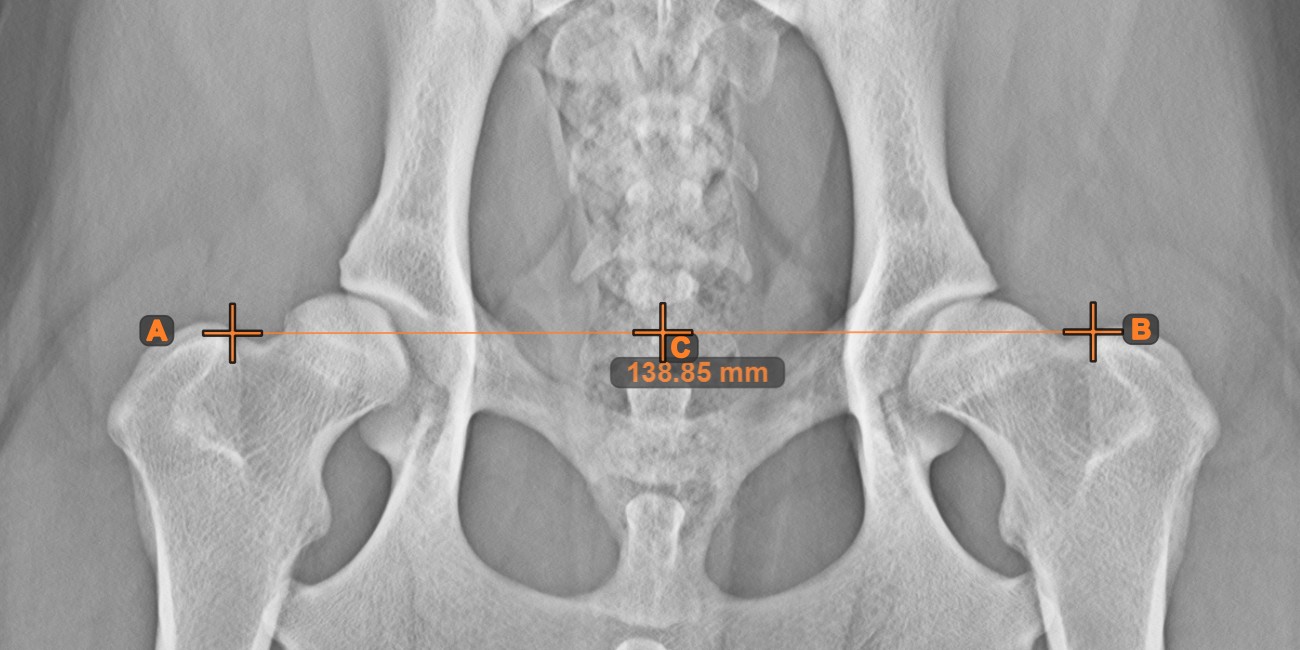

Center Point of Line¶

Identify and mark the center point of a new or existing line measurement on the scene by using the Center Point of Line tool.

Select the tool from the left toolbar and assign it to one of the available mouse buttons. Place the start and end points on the scene, select them from already existing points on the image, or select an already drawn line from the scene. The center point of the line will be automatically calculated and placed on the scene. The center point of each line will always be marked with the letter C.